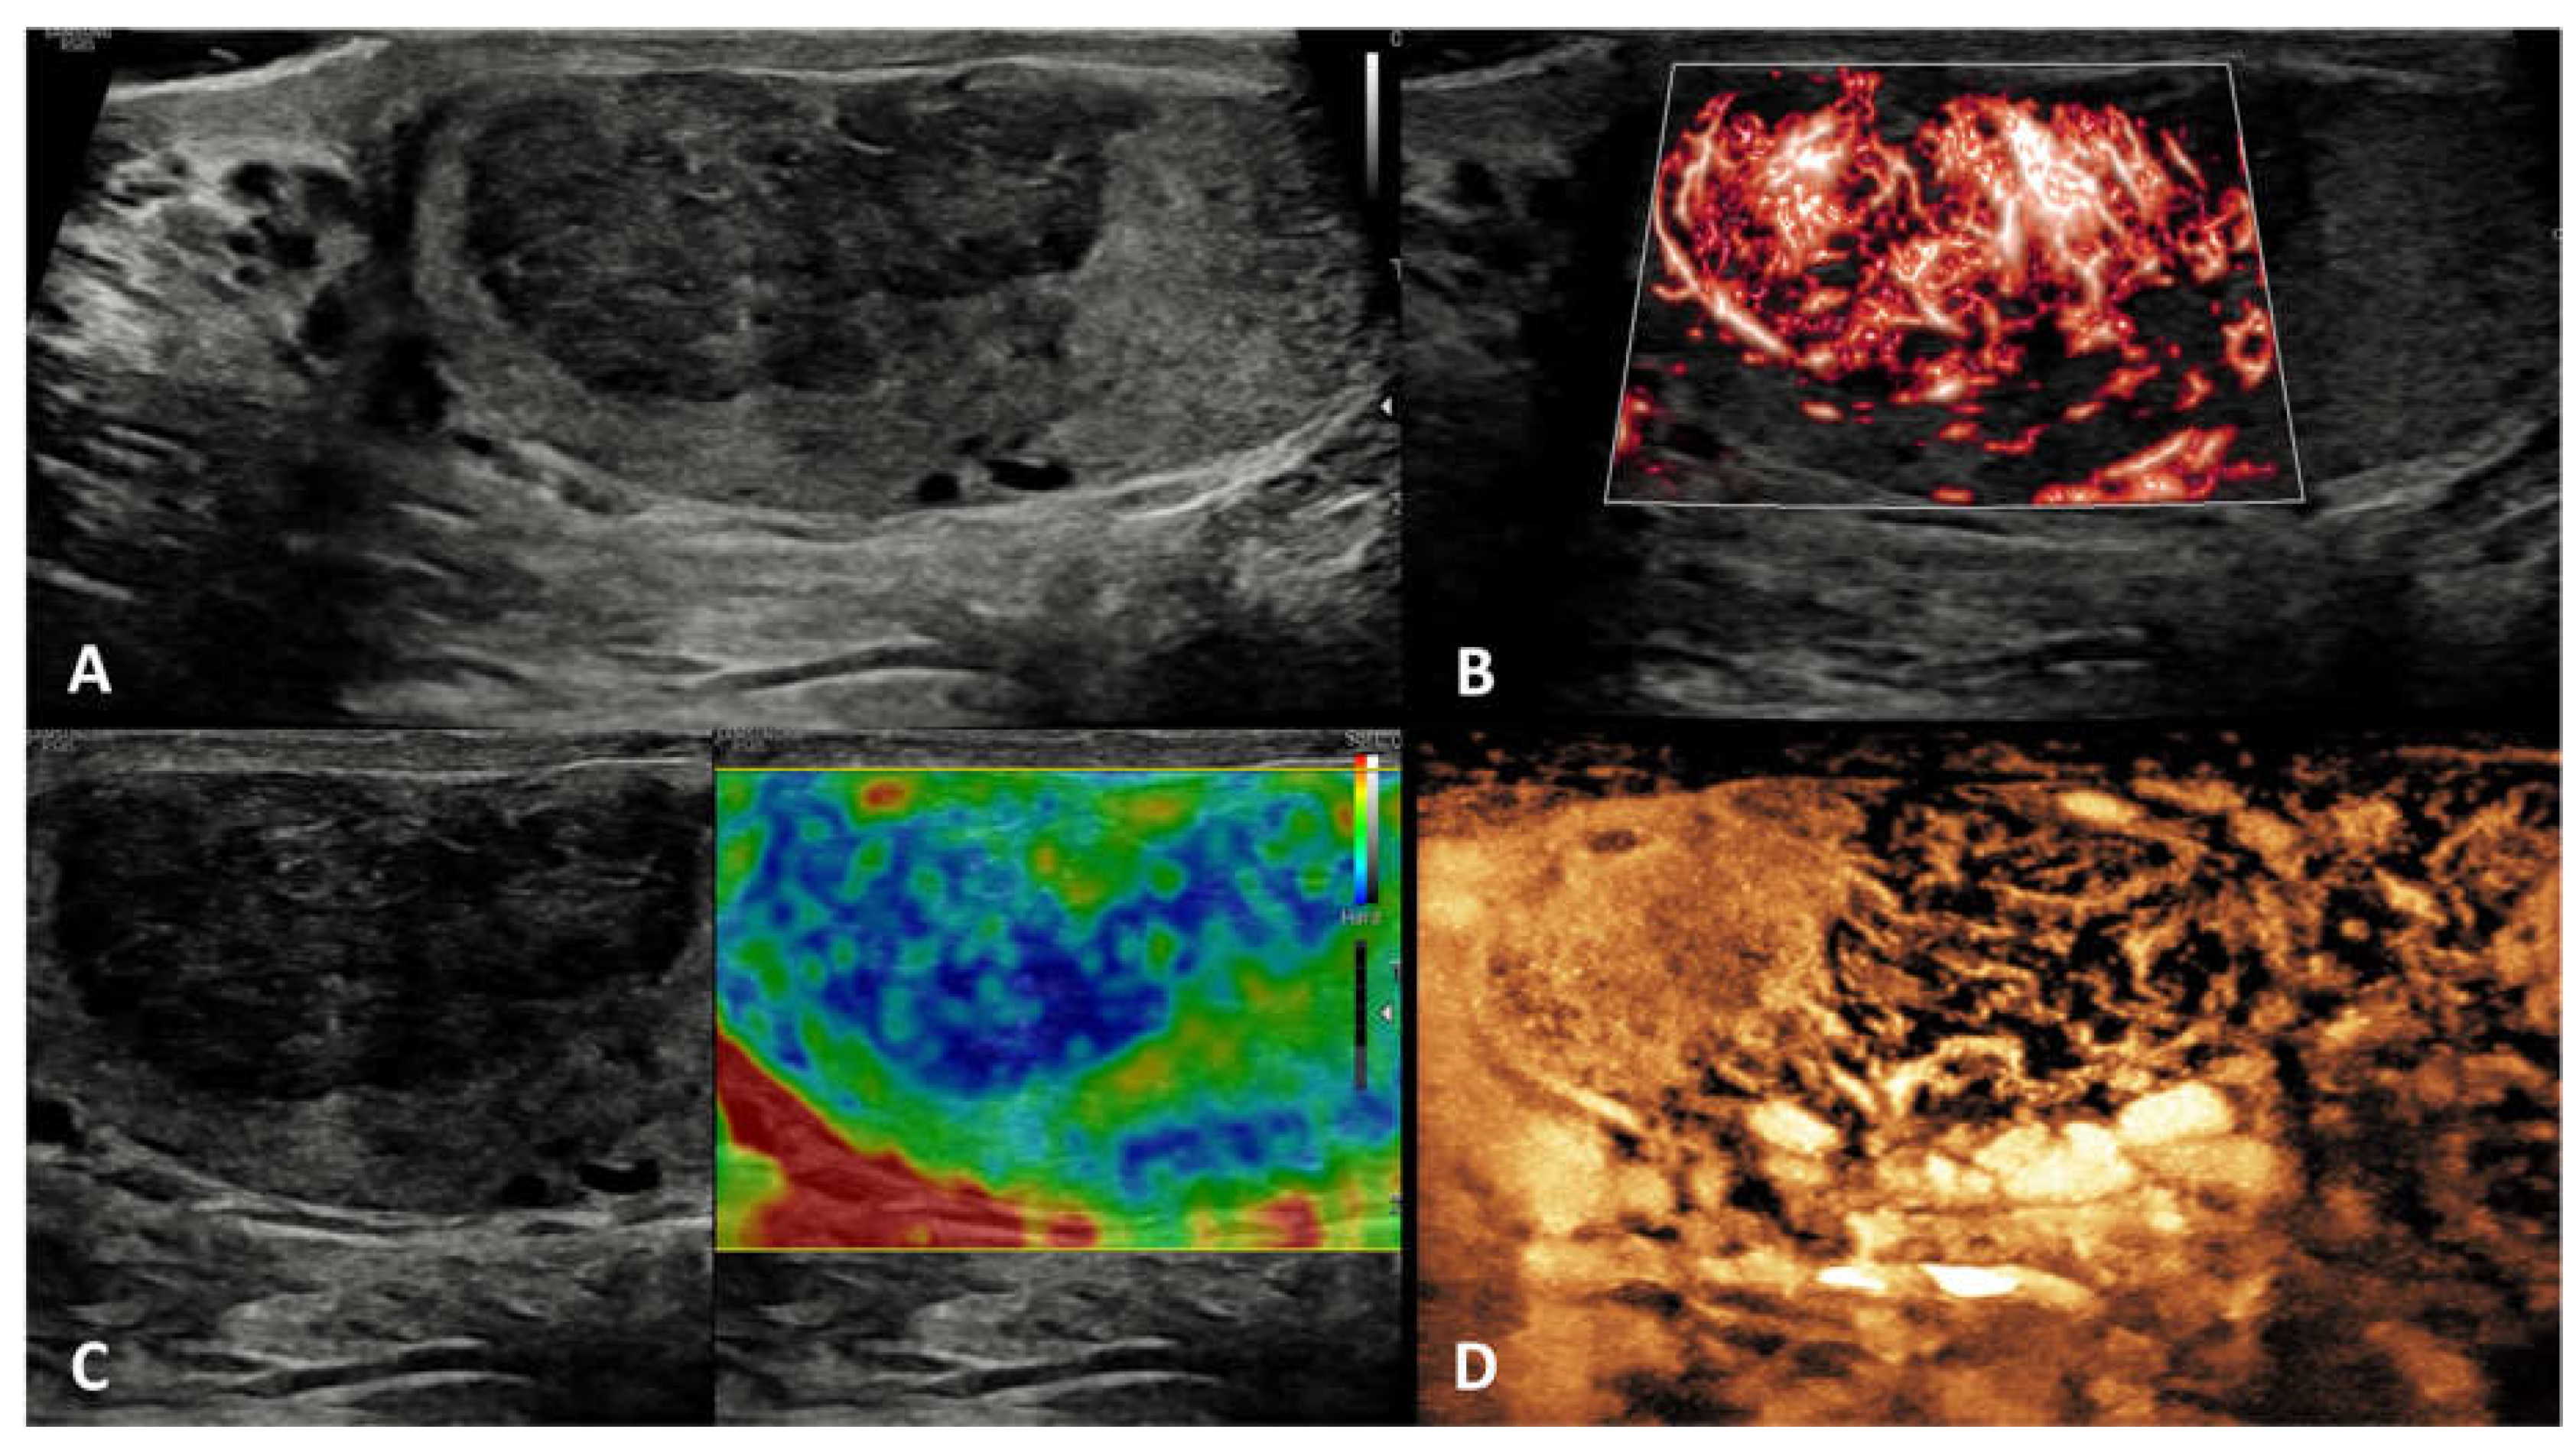

5.8. Viral orchitis and bacterial orchitis (epididymo-orchitis)

| Non-neoplastic intratesticular lesions | |||||

|---|---|---|---|---|---|

| Clinical presentation | GSUS | CDUS | CEUS | SE | |

| Idiopathic (diffuse) granulomatous orchitis | in the context of a multisystem disease; asymptomatic OR painless/painful mass | diffusely hypoechoic testis or hypoechoic areas with ill-defined margins | markedly vascularized |

hyperenhanced | heterogeneous pattern of firmness |